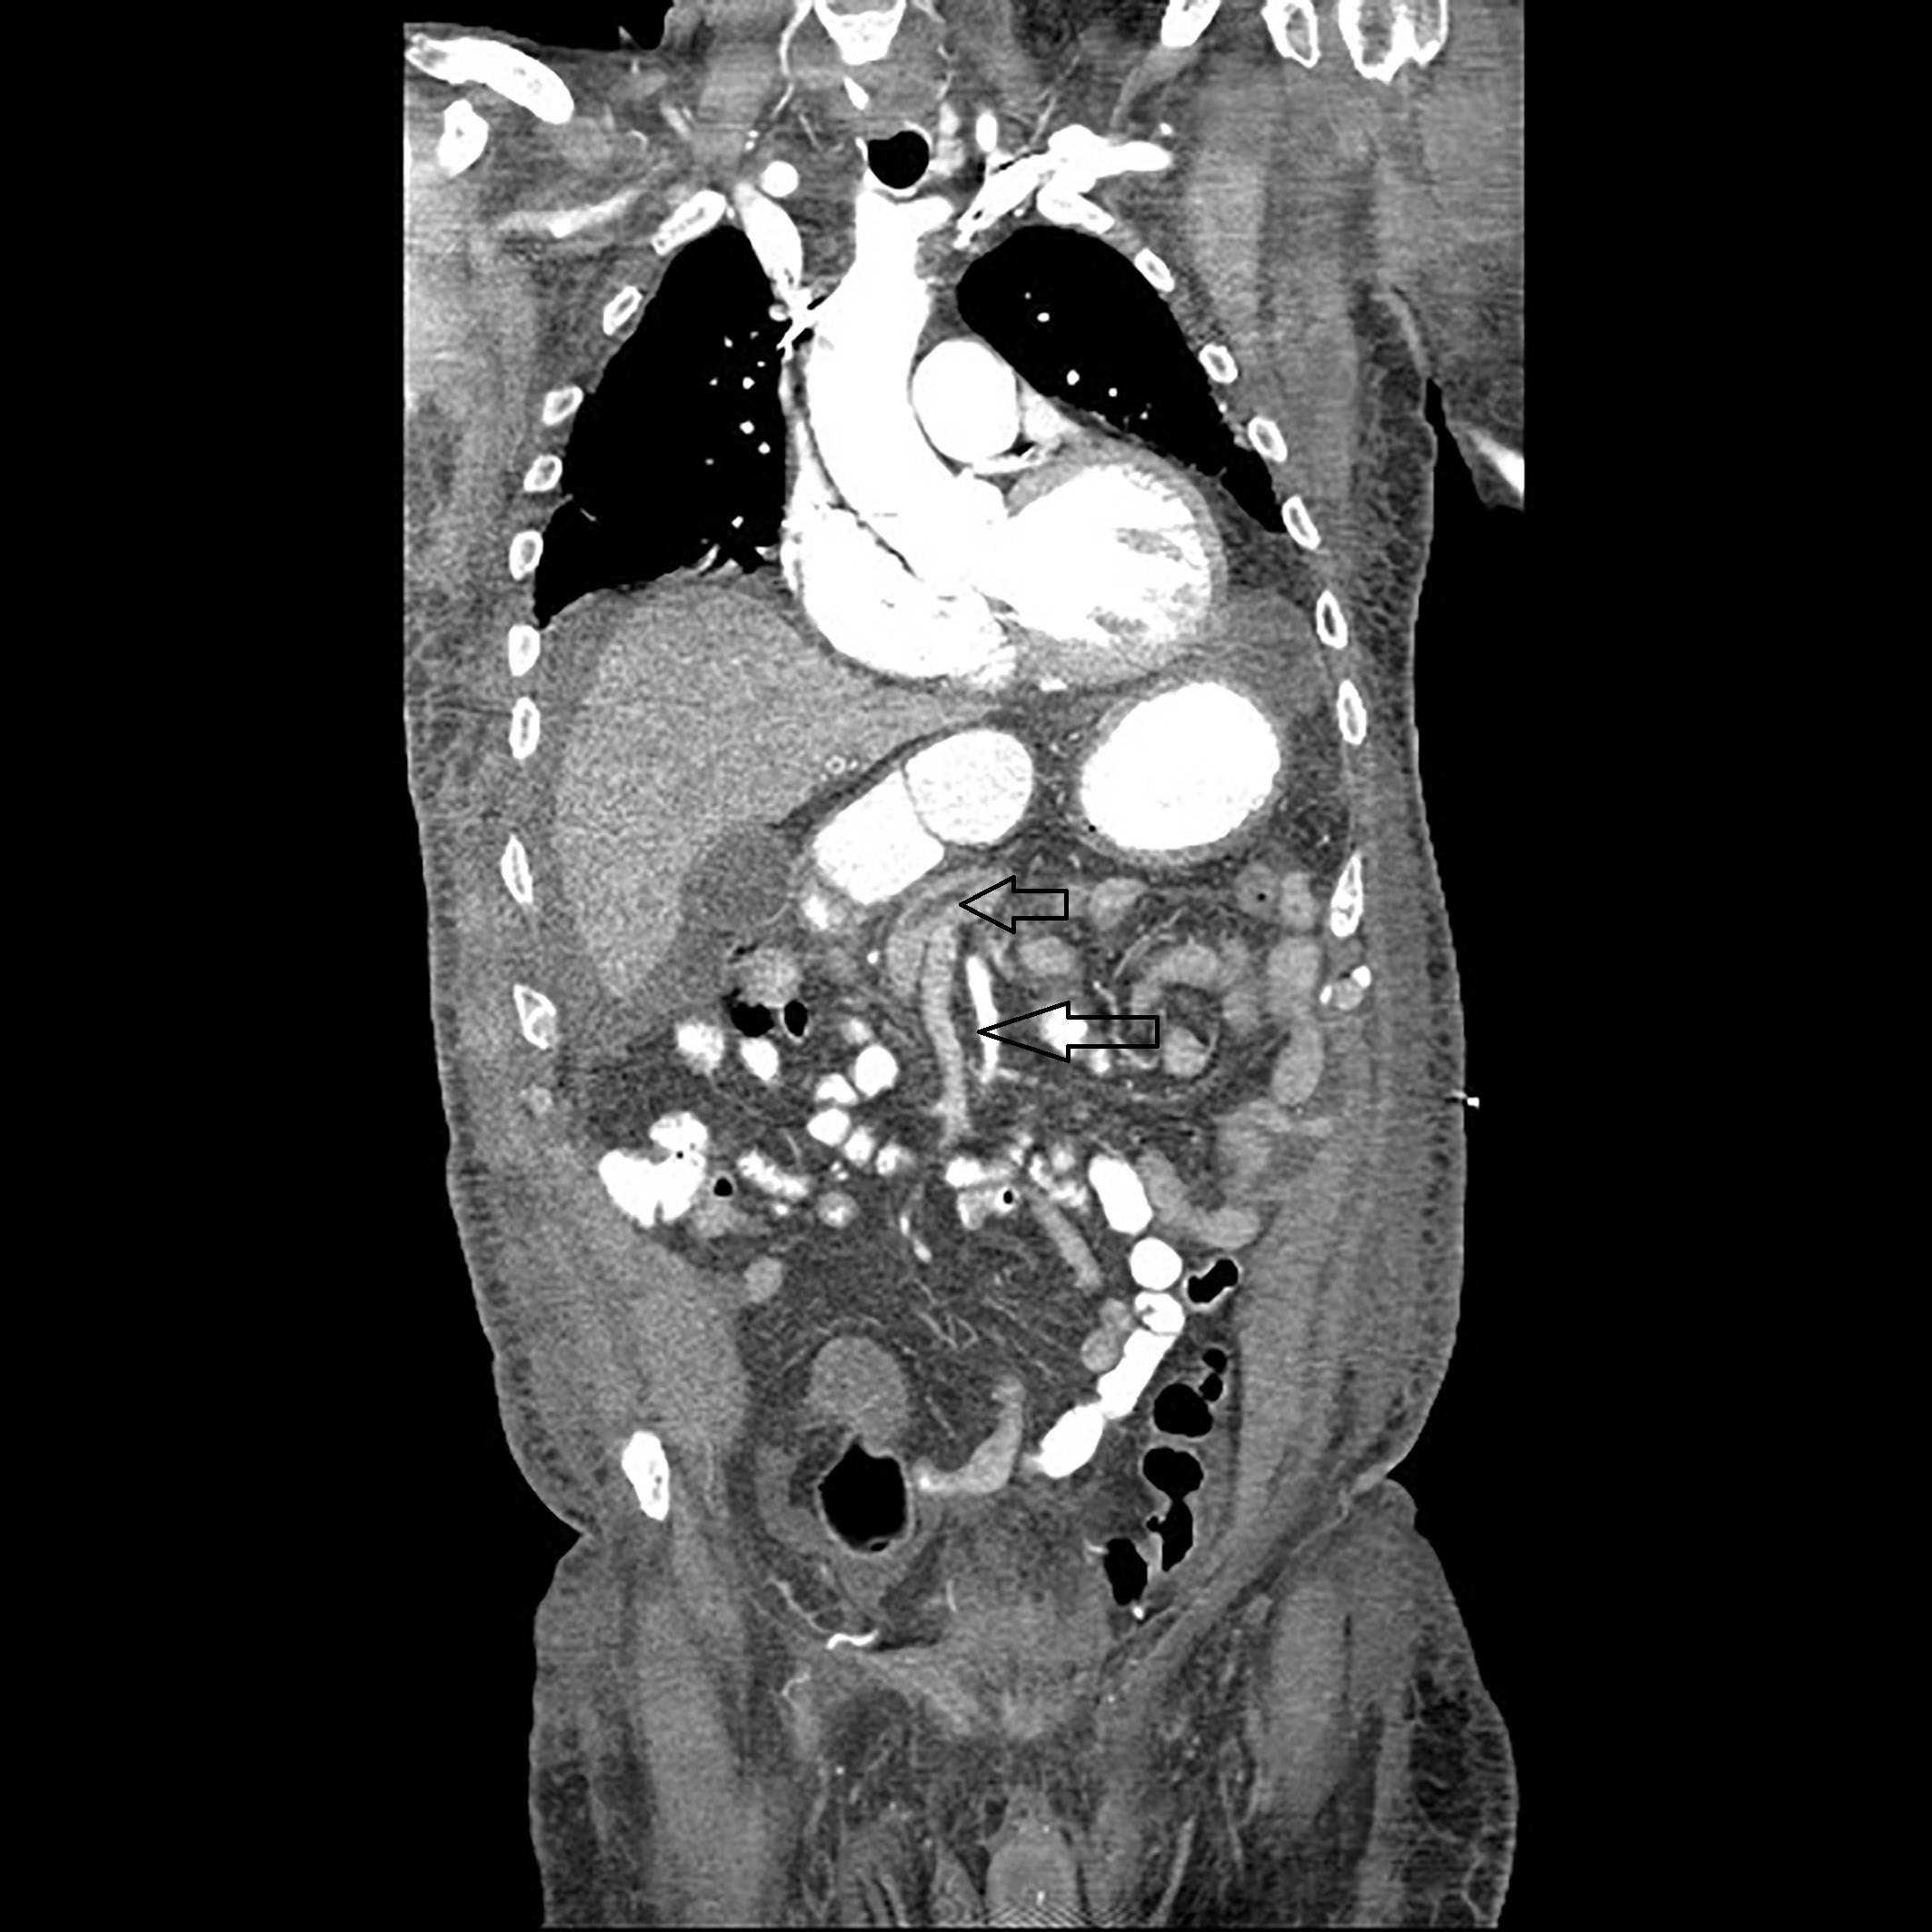

A 74-year- old nursing home resident male with CAD status post cardiac pacemaker, diabetic nephropathy current on hemodialysis and CVA without residual side-effects presented with fever of 102 F and altered mental status. Later he was admitted to the intensive care unit for acute respiratory failure, with bacteremia and septic shock most likely from right thigh abscess. On arrival, he was hypotensive and un-responsive to intravenous fluids. After rapid intubation and central line placement, he was started on aggressive hydration, intravenous vancomycin, pipercillin with tazobactam and pressors. White count 36.6 with left shift, metabolic acidosis on arterial gas with pH of 7.13 and lactic acid trending at 2.5 to 4.5 were noted. Later, a CT scan of right hip showed acute osteomyelitis involving the posterior aspect of the proximal to mid right femur with overlying abscess cavity. A CT scan (abdomen and pelvis) showed presence of gastric wall pneumatosis, transverse duodenal diverticulosis, 2.6cm small bowel lipoma and air/gas lucencies noted within the distal main and left portal veins (Figures 3 & 4). EGD showed mild gastritis in antrum of stomach and single smooth nodule measuring 5-6mm in size in the antrum (Figure 5). Owing to multiple co-morbidities, septic shock and unstable condition, conservative optimal management was made after the extensive family meeting. Later, the family opted for palliative care.

Figure 3 CT scan of the abdomen showing air/gas lucencies noted within the distal main and left portal veins.